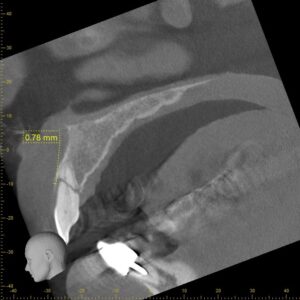

この画像は歯を3次元的に見ることができるCT画像で、明らかな破折している線が確認できました。